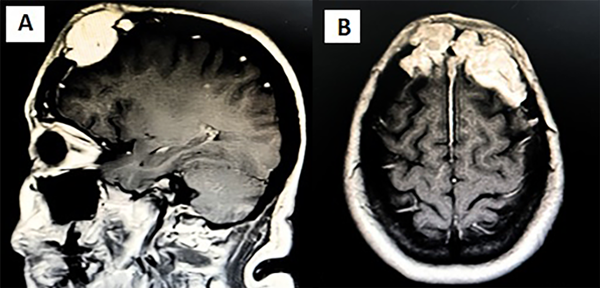

Paciente femenina de 48 años que consultó por el crecimiento acelerado en los últimos 18 meses de una masa frontal de 4 años de evolución, ligeramente dura al tacto, dolorosa, no móvil; sin síntomas neurológicos asociados. Se realizó una resonancia magnética (RM) de encéfalo en la que se reportó una lesión de 23 x 49 x 79 mm, multilobulada, de contornos bien definidos, de localización frontal bilateral y la hoz del cerebro sin efecto masa, la cual se acompaña de un componente extracraneal y leve realce paquimeníngeo (Figura 1). A los meses de la primera evaluación por neurocirugía, se solicita nueva TC que reporta un aumento de tamaño de la lesión: 64 x 43 x 91 mm con compresión de los giros frontales izquierdos, remodelación ósea y apariencia lítica. Al examen físico se detecta una adenopatía cervical izquierda que se reseca. La anatomía patológica del ganglio concluye que es una neoplasia de células plasmáticas (plasmocitoma extramedular) (Figuras 2 y 3).

Figura 1. RM de encéfalo. A) Corte sagital. B) Corte axial.